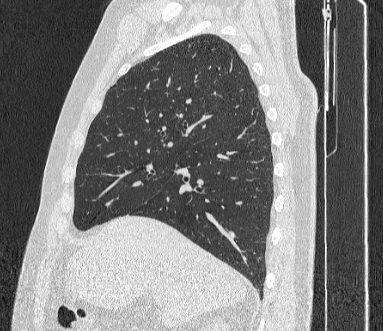

Во время исследования рентгеновская трубка томографа вращается вокруг исследуемой области и производит множество послойных снимков с шагом 0,5-1 мм. Полученные снимки поперечного сечения с помощью компьютерной программы могут быть преобразованы в 3D-изображения исследуемого органа или участка ткани. Это позволяет выявлять практически все заболевания легких на ранних стадиях и назначать своевременное лечение.

В медицинском центре «Доступная медицина» используется современный 128-срезовый компьютерный томограф TOSHIBA AQUILION CXL, на котором проводится сканирование легочной ткани. За счет увеличенного количества детекторов аппарат производит снимки с большой скоростью и минимальной дозой облучения. При этом инновационные цифровые приложения позволяют получить объемные изображения легочной ткани высокой четкости, контрастности и в мельчайших подробностях.

При проведении мультиспиральной КТ легких можно диагностировать различные заболевания, в том числе: